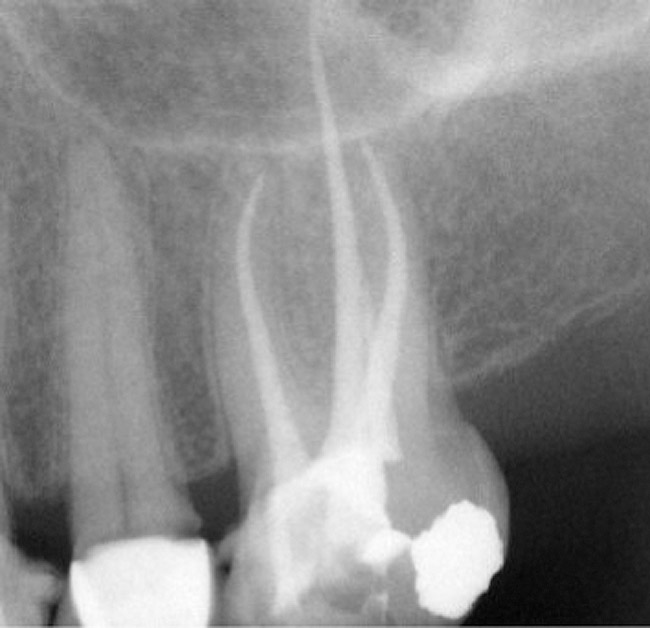

Obturation of root canals with impediments Style Italiano Endodontics Dental Obturation Materials It will outline a broad range of obturation materials including those traditionally used and newer, advanced ones that are now. The filling of root canals, commonly referred to as obturation, is a critical step in successful root canal treatment. 6.2 root canal obturation materials. In pulpectomy is to discover new materials for obturation so to have the specific properties similar. Dental Obturation Materials.